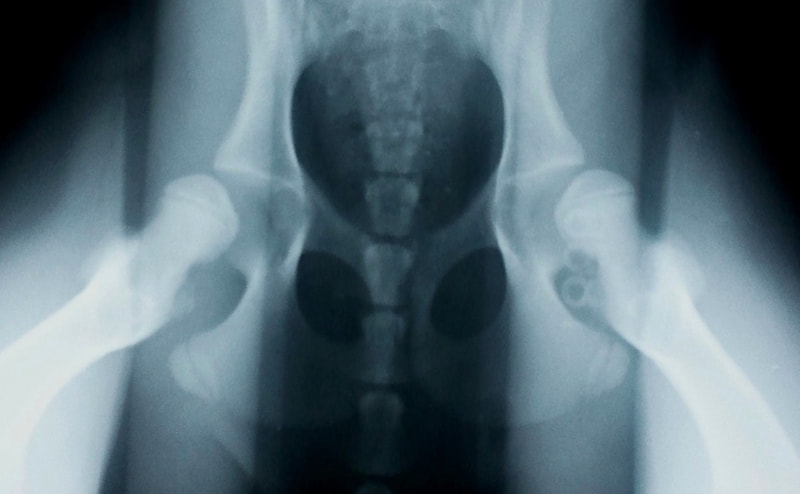

右は股関節伸展像(OFA法)、左は伸延ストレス撮影像で、両者は同じ患者のレントゲン写真です。股関節伸展像(OFA法)では大きな異常は認められませんが、伸延ストレス撮影像では寛骨臼と大腿骨頭の距離が広く、股関節の緩みが認められます。